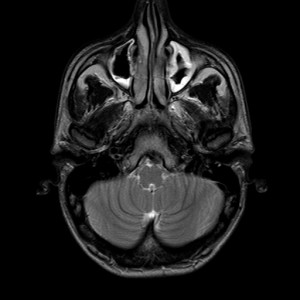

Sono stati i ricercatori della Newcastle University a trovare un rimedio che potrebbe avere qualche possibilità di successo nel trattamento della sinusite. La sinusite, un’infezione dei seni paranasali, colpisce secondo i ricercaotir circa il 10% della popolazione, con dolori al viso e alla testa, perdita dell’olfatto e naso chiuso.

Ciò che rende inefficaci la maggior parte delle cure è un barriera batterica, una sorta di film, che impedisce a tutti gli spray nasali di penetrare oltre il film per eliminare i batteri.